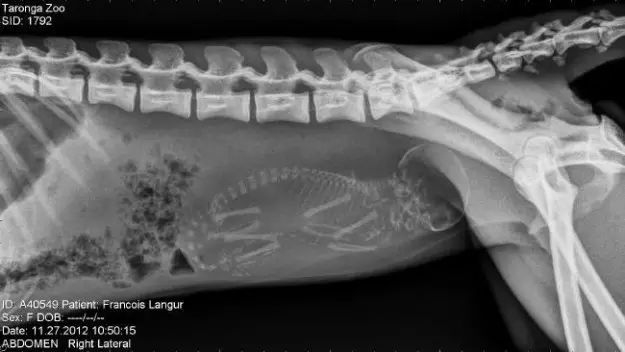

12. 猴子。